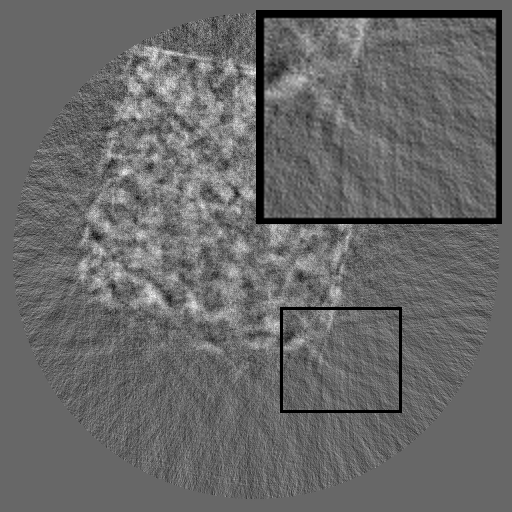

Figure 3: Visual comparison on TomoBank and LoDoPaB under random masking (ratio = 0.8). Rows 1 and 3 show the inpainted sinograms, while Rows 2 and 4 present the corresponding FBP [ramachandran1971three]-reconstructed images.

Table 1 summarizes the quantitative performance of FCDM and all baselines on the TomoBank and LoDoPaB datasets under both random and periodic masks. Figure 3 presents qualitative comparisons at a mask ratio of 0.8, showing both the inpainted sinograms and the reconstructed images obtained using FBP [ramachandran1971three]. Across all settings, FCDM consistently achieves the highest SSIM and PSNR values, demonstrating its strong capability in recovering structural details and suppressing noise-induced artifacts. Visual results in Figure 3 further confirm that FCDM produces smoother and more consistent sinograms, while other methods often exhibit angular streaking or local inconsistencies.